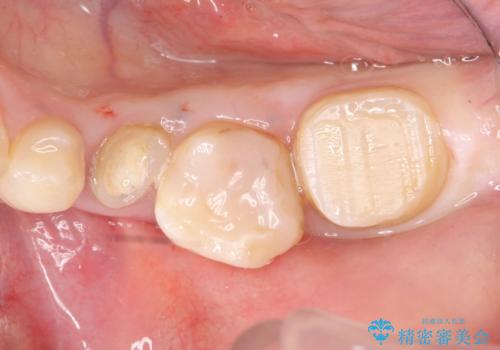

手術後歯茎の治癒を待ち、オールセラミッククラウンによる補綴を行いました。

今回用いたオールセラミッククラウンはジルコニアフレームという白い素材の上にセラミックを盛っているため、審美性が非常に高いのが特徴です。

また、ジルコニアは人工ダイヤモンドの材料にも使われているほど高い強度を持っており、そのためオールセラミッククラウンは審美性だけでなく、奥歯やブリッジの補綴も可能とするクラウンです。